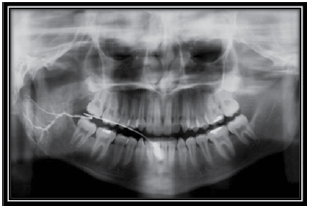

Observe a figura a seguir e responda à questão.

O exame contrastado representado na figura é o de

A

flebografia.

B

sialografia.

C

mielografia.

D

dacricistografia.

E

colecistografia.